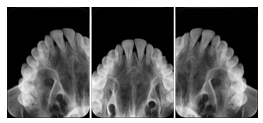

2. A patient requests cosmetic surgery to enhance their facial appearance. The case requires consultation between an orthodontist in New York and an oral surgeon in California. The cephalometric series of 2D projections constructed from the volumetric CT data that is used for the discussion is arranged by a Structured Display for transfer between the two practitioners.

Cephalometric Series Structured Display

Figure OO-2. Cephalometric Series Structured Display